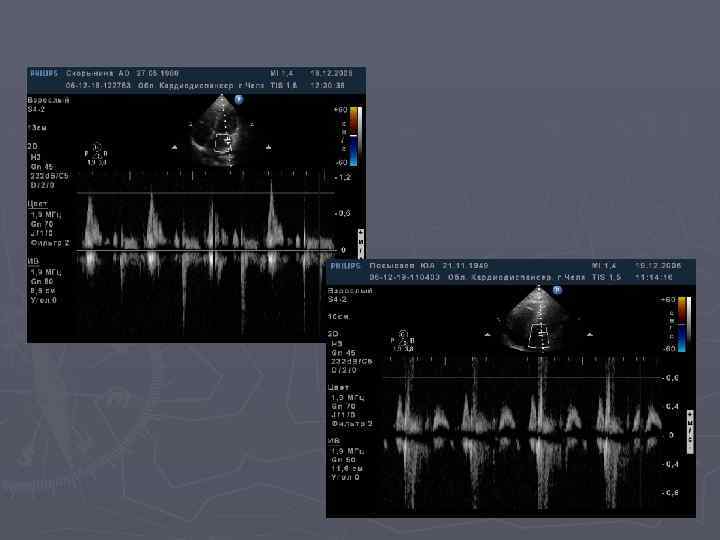

Оценка диастолической функции ЛЖ (ПЖ) по трансмитральному(транстрикуспидальному) потоку. ► ► ► ИВРТ- время изоволюмического расслабления- время от щелчка закрытия АК (КЛА) до щелчка открытия МК(ТК). Норма 65± 20 мс ИВСТ- время изоволюмического сокращения –время от щелчка закрытия МК(ТК) до щелчка открытия АК(КЛА). Норма 65± 20 мс Ve-скорость раннего диастолического наполнения желудочка. Норма 70 -100 см/сек Va- скорость позднего диастолического наполнения желудочка, соответствует систолое предсердия. Норма 45 -70 см/сек. Е/А-отношение скоростей раннего и позднего наполнения желудочков. Норма 1, 0 -1, 5

Оценка диастолической функции по данным тканевого допплеровского исследования ► ► ► ► Расчет на уровне фиброзных колец МК и ТК: IVRTm-время изоволюмичесского миокардиального расслабления(мс) IVCT m- время изоволюмического миокардиального сокращения (мс) DTe m-время замедления волны Е раннего диастолического движения (мс) Em-скорость раннего диастолического движени (см/с) Am-скорость позднего диастолического движения (см/с) Em/Am-отношение скорости раннего и позднего диастолического движения фиброзного кольца ETm-время от начала раннего диастолического движения до конца позднего диастолического движения или продолжительность диастолы (мс)